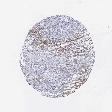

SKIN CANCER - Protein expressioni

A mouse-over function shows sample information and annotation data. Click on an image to view it in a full screen mode. Samples can be filtered based on level of antibody staining by selecting one or several of the following categories: high, medium, low and not detected. The assay and annotation is described here.

Each image is clickable and will lead to virtual microscopy that enables deeper exploration of all samples and also displays staining intensity scores, fraction scores and subcellular localization as well as patient and tissue information for each sample.

Antibody CAB000142

Basal cell carcinoma

Squamous cell carcinoma, NOS

Squamous cell carcinoma, metastatic, NOS

Squamous cell carcinoma in situ, NOS

Adnexal tumor, benign